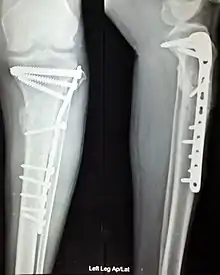

Orthopedic implants to repair fractures to the radius and ulna. Note the visible break in the ulna. (right forearm)

Anterior and lateral view x-rays of fractured left leg with internal fixation after surgery